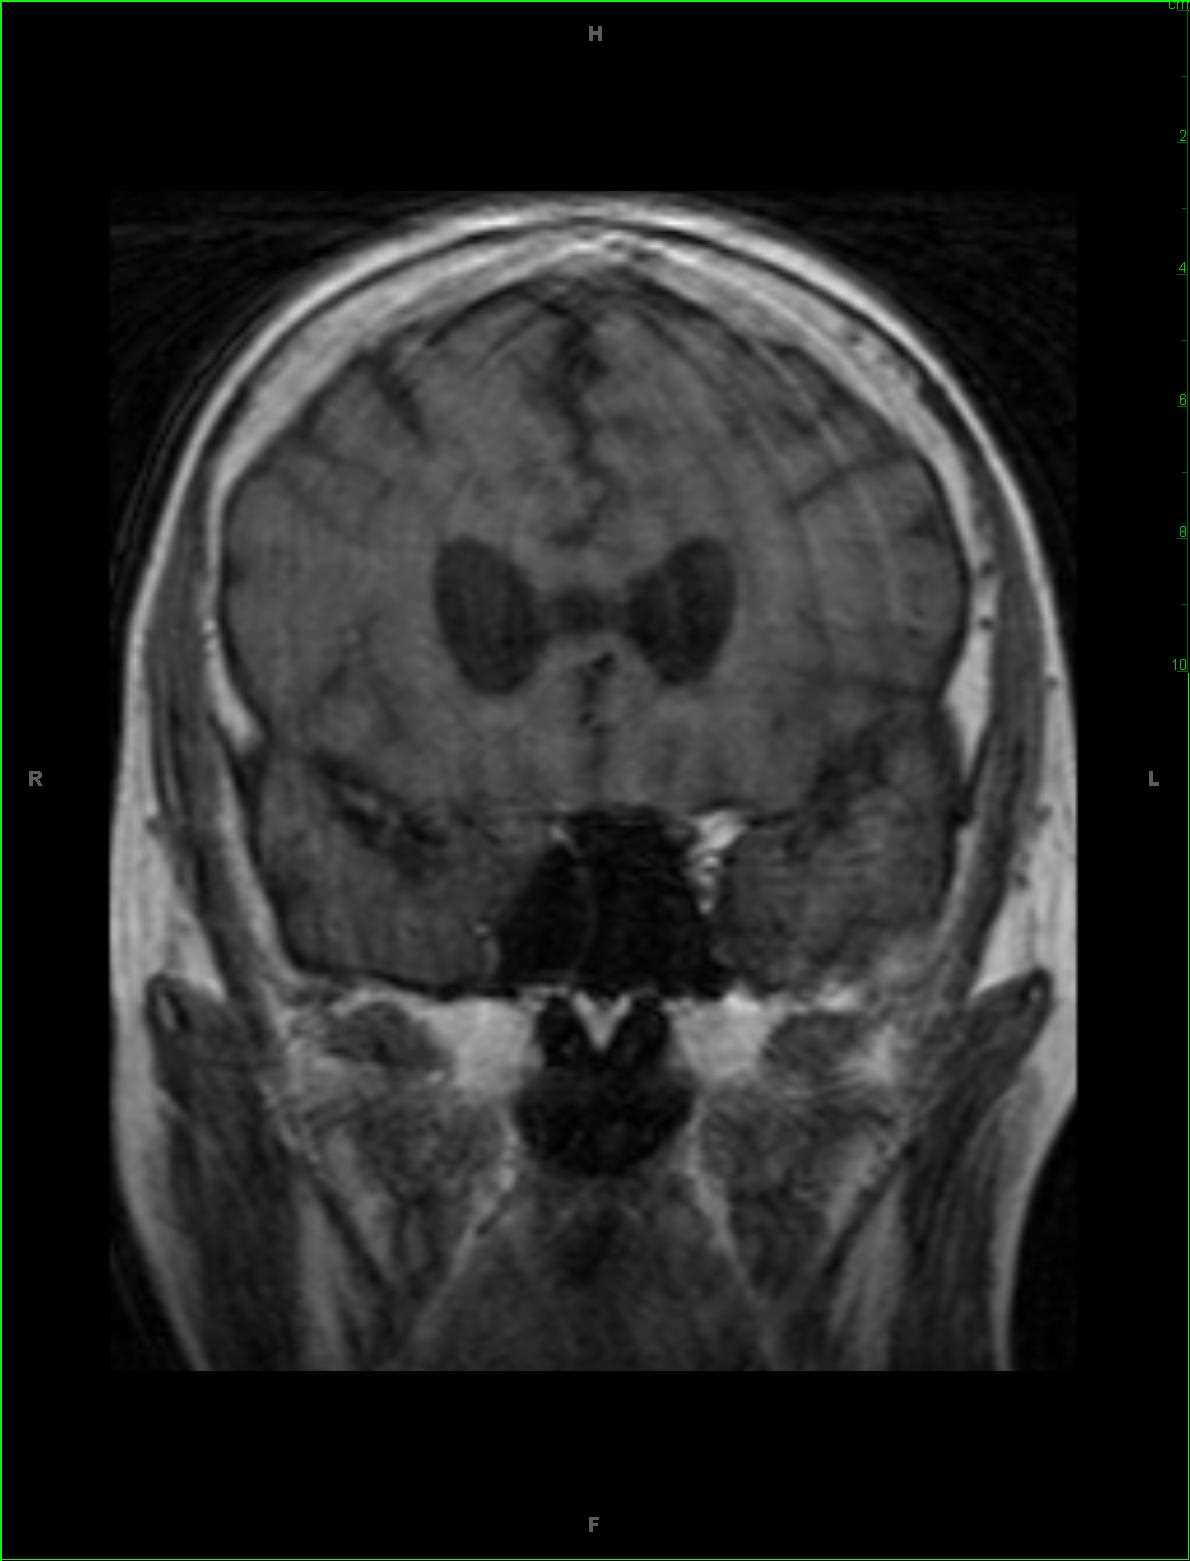

48-year-old female who attempted suicide by overdosing on acetaminophen. There is hyperintense FLAIR signal abnormality within the dorsomedial aspect of the thalami and extending into the midbrain. There is abnormal diffusion restriction at the sites without contrast enhancement. Given the stated clinical history, the findings are most compatible with acute hepatic encephalopathy in the setting of acetaminophen toxicity. Hepatic encephalopathy may be either acute or chronic. Acute cases typically arise in the setting of acute hepatic failure, such as in this case. Chronic cases tend to occur in patients who undergone prior portosystemic bypass without associated intrinsic hepatocellular disease or in patients with hepatocellular dysfunction and portosystemic shunting. Classic MR imaging abnormalities include high T1 signal intensity within the globus pallidus with mild cases demonstrating T2 FLAIR symmetrically hyperintense signal in the insula, thalami, and posterior limbs of the internal capsules. Diffusion signal abnormality may be present and can reverse if therapy for the underlying acute decompensation is instituted early. The extent and severity of the FLAIR and diffusion-weighted imaging correlates with the plasma ammonia level.